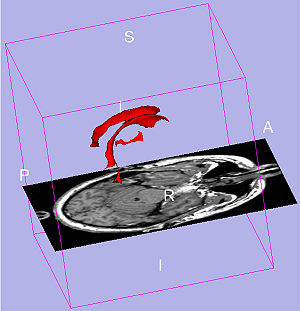

Publication: Int J Comput Assist Radiol Surg. 2016 Mar;11(3):473-81. PMID: 26183148 Authors: De Momi E, Ferrigno G, Bosoni G, Bassanini P, Blasi P, Casaceli G, Fuschillo D, Castana L, Cossu M, Lo Russo G, Cardinale F. Institution: Department of Electronics, Information and Bioengineering (DEIB), Politecnico di Milano, Milan, Italy. Background/Purpose: Image guidance is widely used in neurosurgery. Tracking systems (neuronavigators) allow registering the preoperative image space to the surgical space. The localization accuracy is influenced by technical and clinical factors, such as brain shift. This paper aims at providing quantitative measure of the time-varying brain shift during open epilepsy surgery, and at measuring the pattern of brain deformation with respect to three potentially meaningful parameters: craniotomy area, craniotomy orientation and gravity vector direction in the images reference frame. Methods: We integrated an image-guided surgery system with 3D Slicer, an open-source package freely available in the Internet. We identified the preoperative position of several cortical features in the image space of 12 patients, inspecting both the multiplanar and the 3D reconstructions. We subsequently repeatedly tracked their position in the surgical space. Therefore, we measured the cortical shift, following its time-related changes and estimating its correlation with gravity and craniotomy normal directions. Results: The mean of the median brain shift amount is 9.64 mm ([Formula: see text] mm). The brain shift amount resulted not correlated with respect to the gravity direction, the craniotomy normal, the angle between the gravity and the craniotomy normal and the craniotomy area. Conclusions:Our method, which relies on cortex surface 3D measurements, gave results, which are consistent with literature. Our measurements are useful for the neurosurgeon, since they provide a continuous monitoring of the intra-operative sinking or bulking of the brain, giving an estimate of the preoperative images validity versus time. |